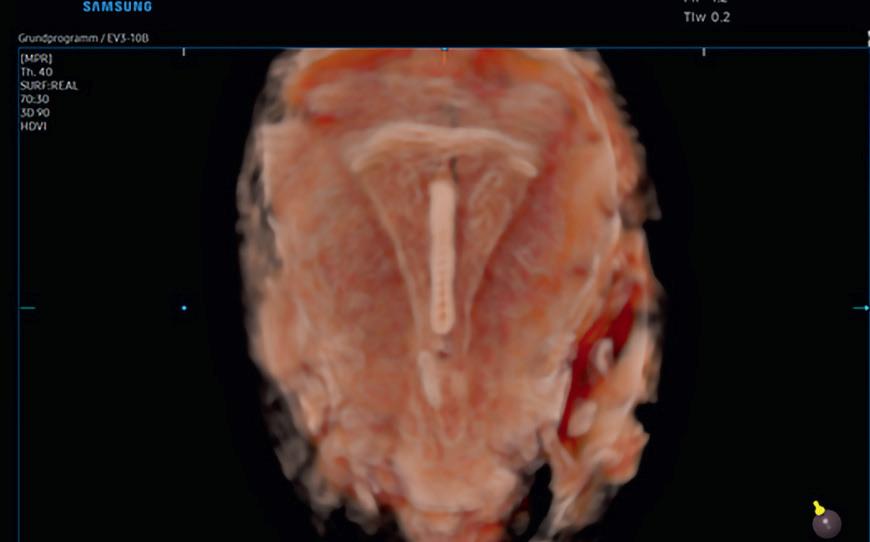

Step Up Confidence with Samsungs New V-series

Enriched diagnostic features with accuracy and precision

The V7 system comes with advanced features for women’s health that assist in precise diagnosis and increasing throughput. The V7’s variety of features and user-friendly interface aid in significantly improving the healthcare professionals’ daily ultrasound examination experience.

Redefined Imaging Technologies

Powered by Crystal ArchitectureTM (CrystalBeamTM, CrystalLiveTM

Sophisticated 2D Image Processing&Detailed Color Expression

Shadow HDRTM, HQ-VisionTM, ClearVision, S-flowTM, MV-FlowTM, LumiFlowTM

Women´s Health

BiometryAssistTM, 5D FollicleTM, Limb VolTM, 5D CNS+TM, 5 NTTM, Heart ColorTM, Labor AssistTM, E-CervixTM, IOTA-ADNEX, HDVI, RealisticVueTM, CrystalVueTM, CrystakValueFlowTM

RealisticVue

Re engineered Workflow and Enhanced Customization

TouchGesture, HelloMomTM, TouchEdit, QuicckPreset, Expanded view, EzCompareTM, EzExams+

Comfort Design

14-inchTilting Touchscreen, 23.8-inch LED Monitor, Contextual Button, QuickSave, BatteryAssistTM, Cooling System, Adjustable Control Panel, Tranduceer Cable Hook, Endocavity Transducer Holder, Gel Warmer

5D Follicle